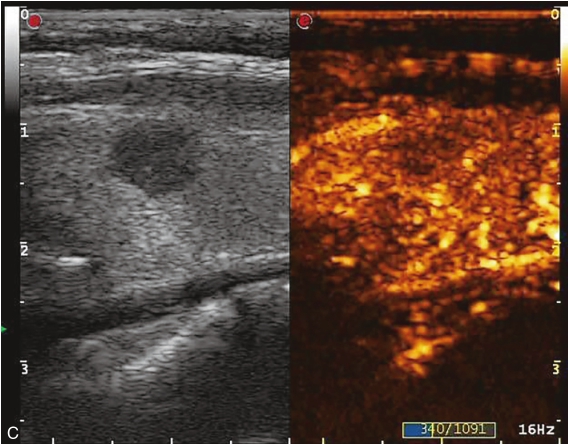

甲状腺右叶中部可见一个肿块,大小约为2.6cm×1.8cm×1.8cm,形状尚规则,边界尚清楚,内部为低回声,分布不均匀,后方回声无变化,CDFI显示肿块内可见丰富的血流信号,见图1-9-1。

图1-9-1 甲状腺髓样癌常规超声图像

A.甲状腺右叶低回声结节纵切面灰阶超声图像;B.甲状腺右叶低回声结节横切面灰阶超声图像;C.CDFI图像